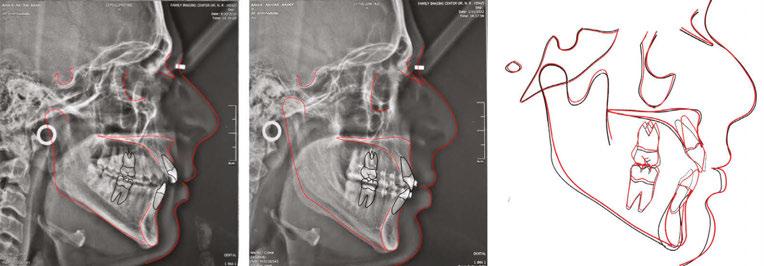

The current clinical report successfully uses infragomatic miniscrews to intrude and retract posterior segments in an adult high-angle Class II malocclusion, which also succeeded in the correction of sagittal, transverse, and vertical discrepancies.

The panoramic X-ray showed a full complement of teeth, a left horizontally impacted third molar, along with the three other third molars (Figure 2F). The pretreatment cephalometric analysis revealed a skeletal Class II measurement of an ANB of 6.8° with a retrognathic mandible measuring aSNB of 76.6°. The mandible had a hyperdivergent growth pattern of 58.35% with a long anterior face height of 130.6 mm (Figure 3A). The maxillary incisors showed protrusion of .9.5mm to APOg with a proclination of 115.8°, while the mandibular incisors were retrusive with an APOg mea surement of .4 mm and retro clined to 84°.

Figures 3A-3C: Cephalometric tracing before and after treatment and superimposition Figures 4A-4E: Infrazygomatic miniscrews inserted in the upper jaw Figures 5A-5D: Finishing and detailing the occlusion with a progress pan oramic X-ray B. C.Wraparound Hawley Retainers provided retention, which encouraged further molar eruption and intercuspation. Once molar intercuspation completes, new thermoelastic refiners would be used to prevent molars from over eruption.

Cephalometric superimposition of the pre- and-post-tracings showed an overall improvement among multiple cephalometric measurements, including, but not limited to, the refinement of the maxillary and mandibular incisors’ positions. The maxillary incisors decreased their proclamation from 115° to 107.3°, and their anteroposterior position decreased from 9.5 mm to 3.4 mm. The mandibular incisor IMPA increased from 84° to 91.8°, while the anteroposterior position increased from 0.4 mm to 1.9 mm.

The lower lip to the E-line improved from the mandibular incisor proclination, and the mandibular counterclockwise rota tion provided by the intrusion of the posterior maxillary segment. The patient’s anterior face height decreased dramatically by 3.07 mm. The Frankfort mandibular plane decreased by 2.7° as well as an improvement of the facial axis by 2.6°.